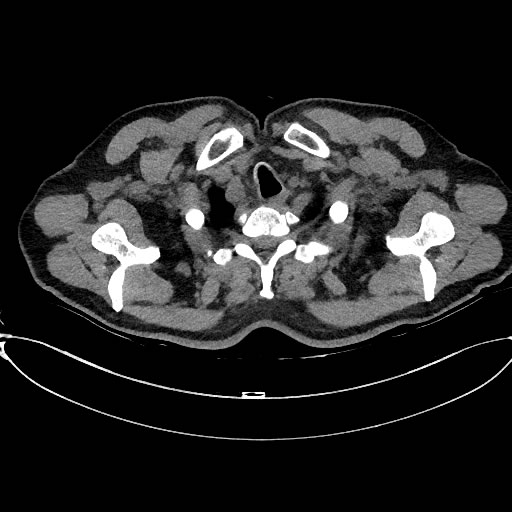

Image: 1